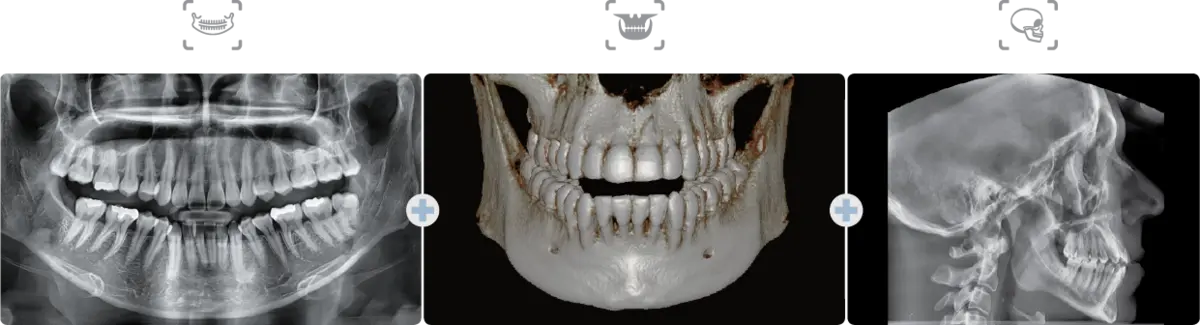

진료 과목과 예산에 맞는 장비 구성안을 제안합니다. CBCT, 파노라마, 유니트 체어, 멸균기, 석션 시스템 등 필수 장비부터 구강스캐너, CAD/CAM 등 디지털 장비까지 — 진료실 면적과 전력 용량을 고려한 최적의 배치 도면을 제공합니다.

개원컨설팅 관련 이미지